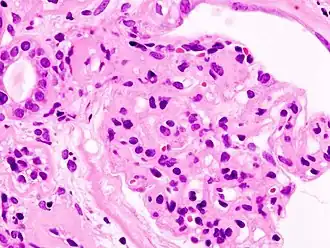

Гистопатологическая картина диабетического гломерулосклероза с нефротическим синдромом.